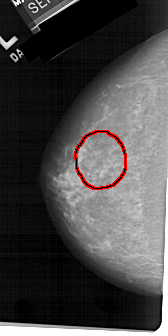

A_1224_1.LEFT_CC

LEFT_CC LINES 5026 PIXELS_PER_LINE 2506 BITS_PER_PIXEL 12 RESOLUTION 43.5 OVERLAY

FILE: A_1224_1.LEFT_CC.OVERLAY

TOTAL_ABNORMALITIES 1

ABNORMALITY 1

LESION_TYPE MASS SHAPE IRREGULAR MARGINS SPICULATED

ASSESSMENT 4

SUBTLETY 3

PATHOLOGY MALIGNANT

TOTAL_OUTLINES 1

BOUNDARY